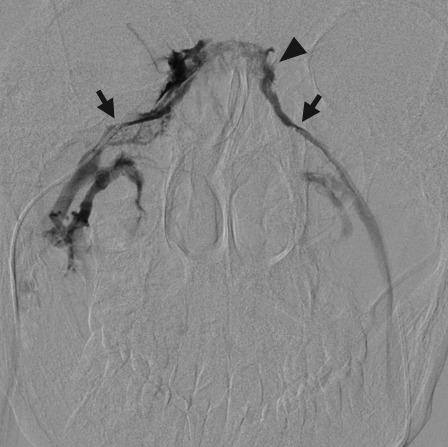

Venous sampling is the gold standard for localizing abnormal hormone secretion in several endocrine disorders. The most common indication for venous sampling is in the workup of primary aldosteronism, adrenocorticotropic hormone-dependent Cushing's syndrome, and hyperparathyroidism. In experienced hands, venous sampling is safe and accurate. This review discusses the role of venous sampling in the workup of endocrine disease, describing the underlying anatomy and pathophysiology, as an understanding of these concepts is essential for technical and clinical success.